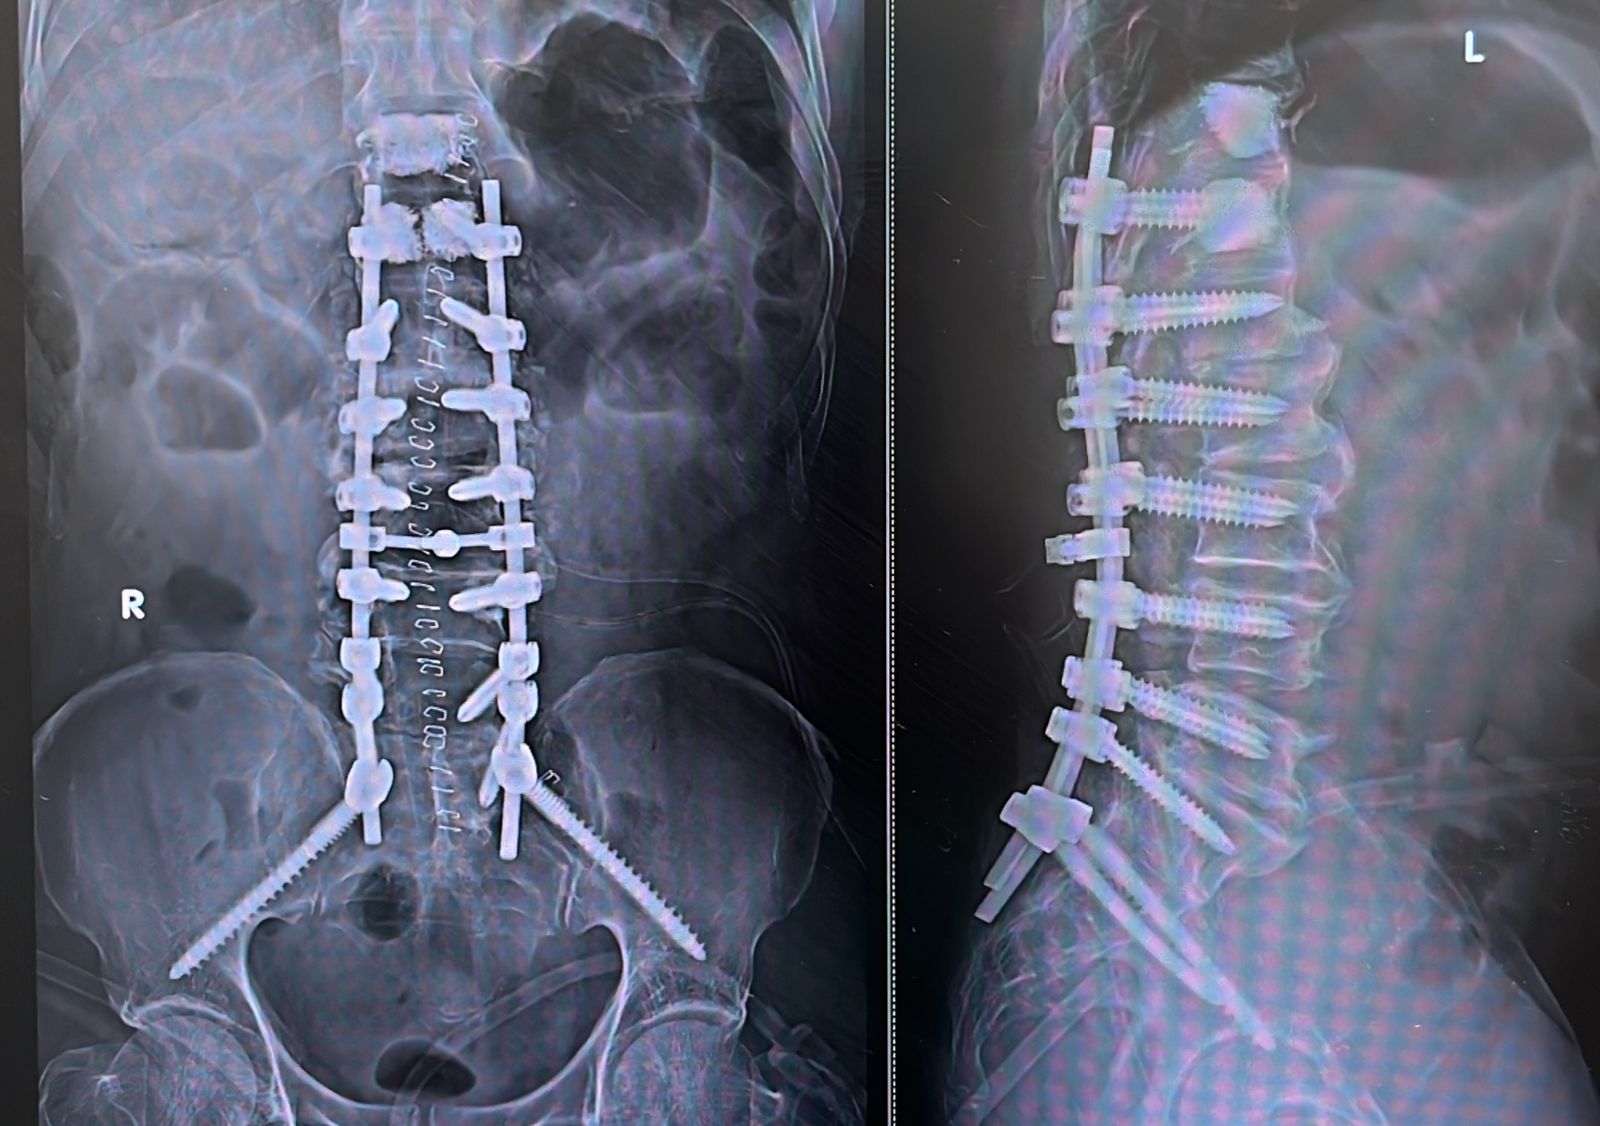

ডক্টর বিদ্যাধরের নেতৃত্বে সার্জারির ব্যবস্থা করা হয়। যার মধ্যে ছিল স্কোলিওসিস কারেকশন, স্নায়ুর উপর থেকে চাপমুক্ত করা (ডিকমপ্রেশন) এবং ইনস্ট্রুমেন্টেড স্ট্যাবিলাইজেশন, অর্থাৎ অস্তিবন্ধন করে মেরুদণ্ডকে স্থিতিশীল করা। সার্জারির সময় অত্যন্ত আধুনিক প্রযুক্তিতে, রোবোটিক গাইডেন্সের মাধ্যমে, সিমেন্ট অগমেন্টেশন, দুটি S2 Alar Iliac স্ক্রু এবং পেডিকেল স্ক্রু বসানো হয়।

অস্ত্রোপচারের পরে।